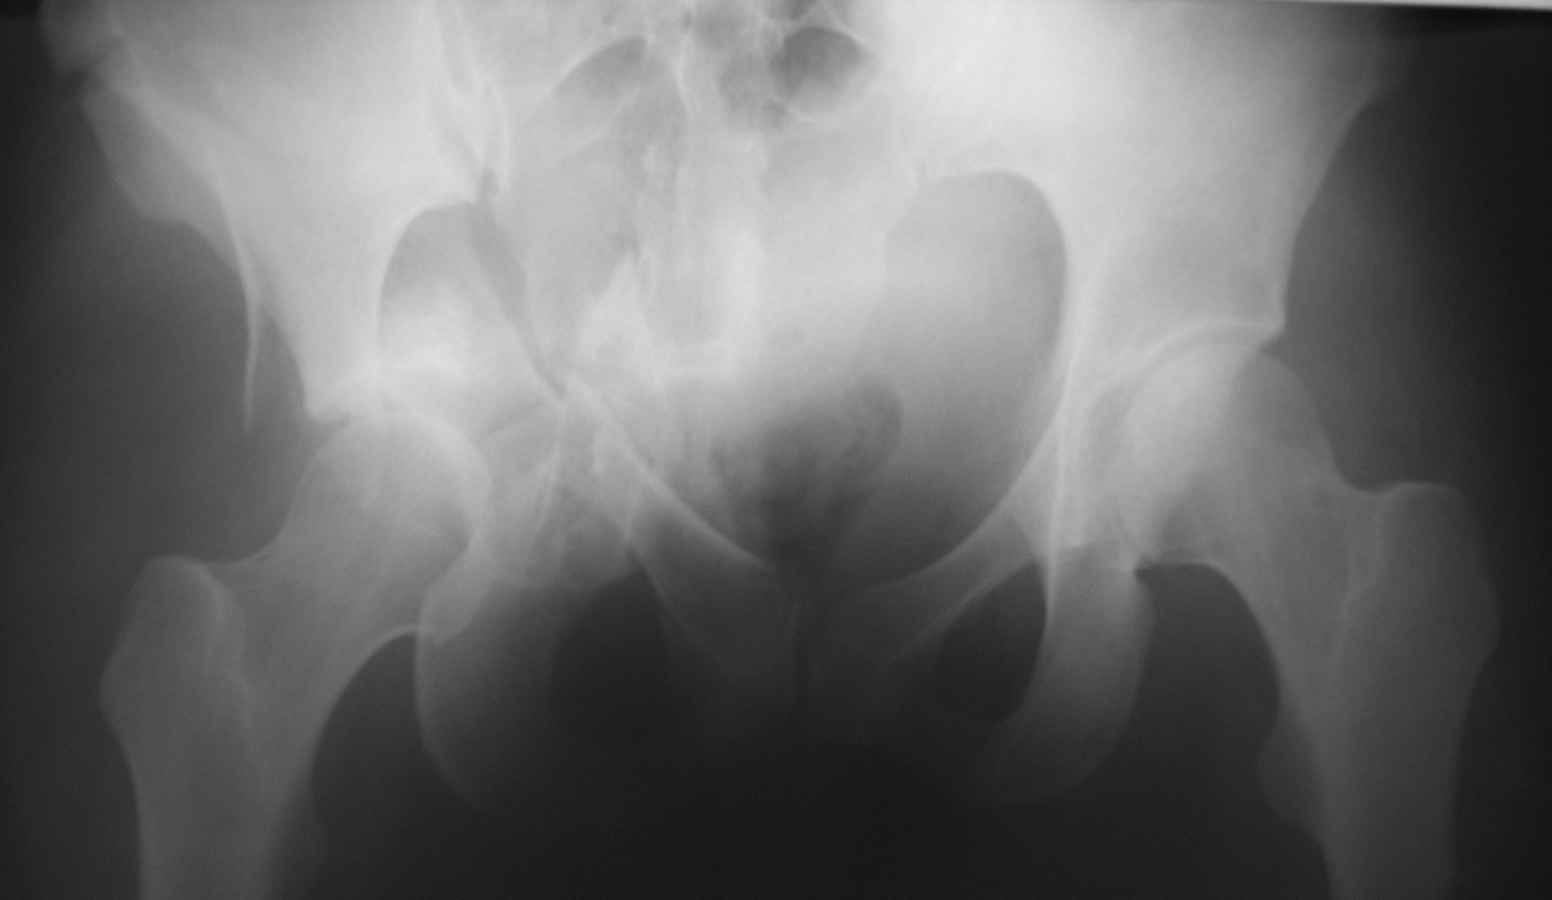

Это не "цетральный вывих", а двухколонный перелом вертлужной впадины. Лучше прооперировать, я бы выбрал подвздошно бедренный доступ, хотя можно и из бокового чрезвертельного.

Оскольчатый двухколонный перелом, лучше отправить пациента туда, где занимаются лечением "центральных вывихов" бедра.

Тут перелом достаточно сложный и говорить о характере перелома можно после дополнительных методов исследования. Нужны проекции Judet для оценки передней и задней колонн (перелома передней и задней колонн видны и на этом снимке, но характер их перелома и смещение лучше видны в специальных порекциях). Нужно КТ исследование.

Большое спасибо за содержательные советы. Вот снимок при поступлении.

К сожалению, даже по представленным рентгенограммам видно, что ничего особенного после так называемого Вами вправления не изменилось. Если сделать КТ или МРТ картина будет ещё более удручающей. Прочитайте внимательнее пост Батала Алексеевича Шушании и прислушайтесь к его совету, потому, что время данной ситуации работает против пациента.